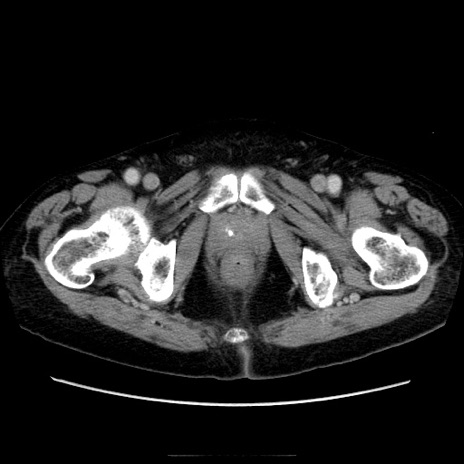

症例21(横断像)

【症例】70歳代男性

【主訴】腹痛

【現病歴】肝硬変・肝細胞癌にてかかりつけの方。約9時間前に食後より腹痛出現。症状が徐々に増悪し、嘔吐出現したため来院。

【既往歴】肝硬変、肝細胞癌(RFA、TACE後)

【身体所見】意識清明、表情苦悶様、BT 36℃、BP 129/78mmHg、P 88bpm、SpO2 97%(RA)、右上腹部から心窩部にかけて圧痛あり、反跳痛なし、筋性防御あり。

【データ】WBC 5800、CRP 0.16